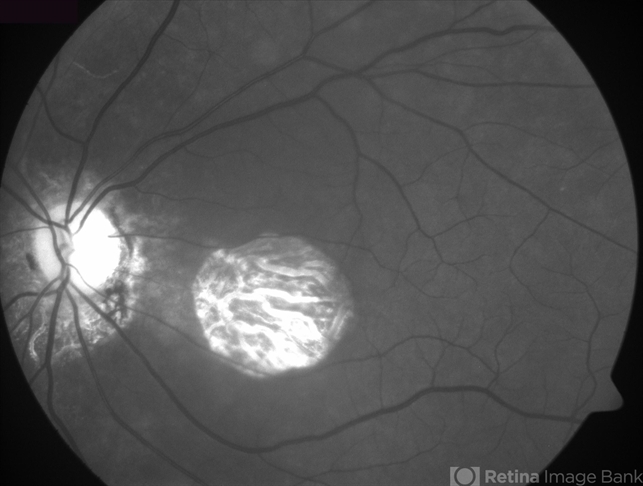

- geographic atrophy, red-free

- Geographic atrophy due to AMD - red free image.